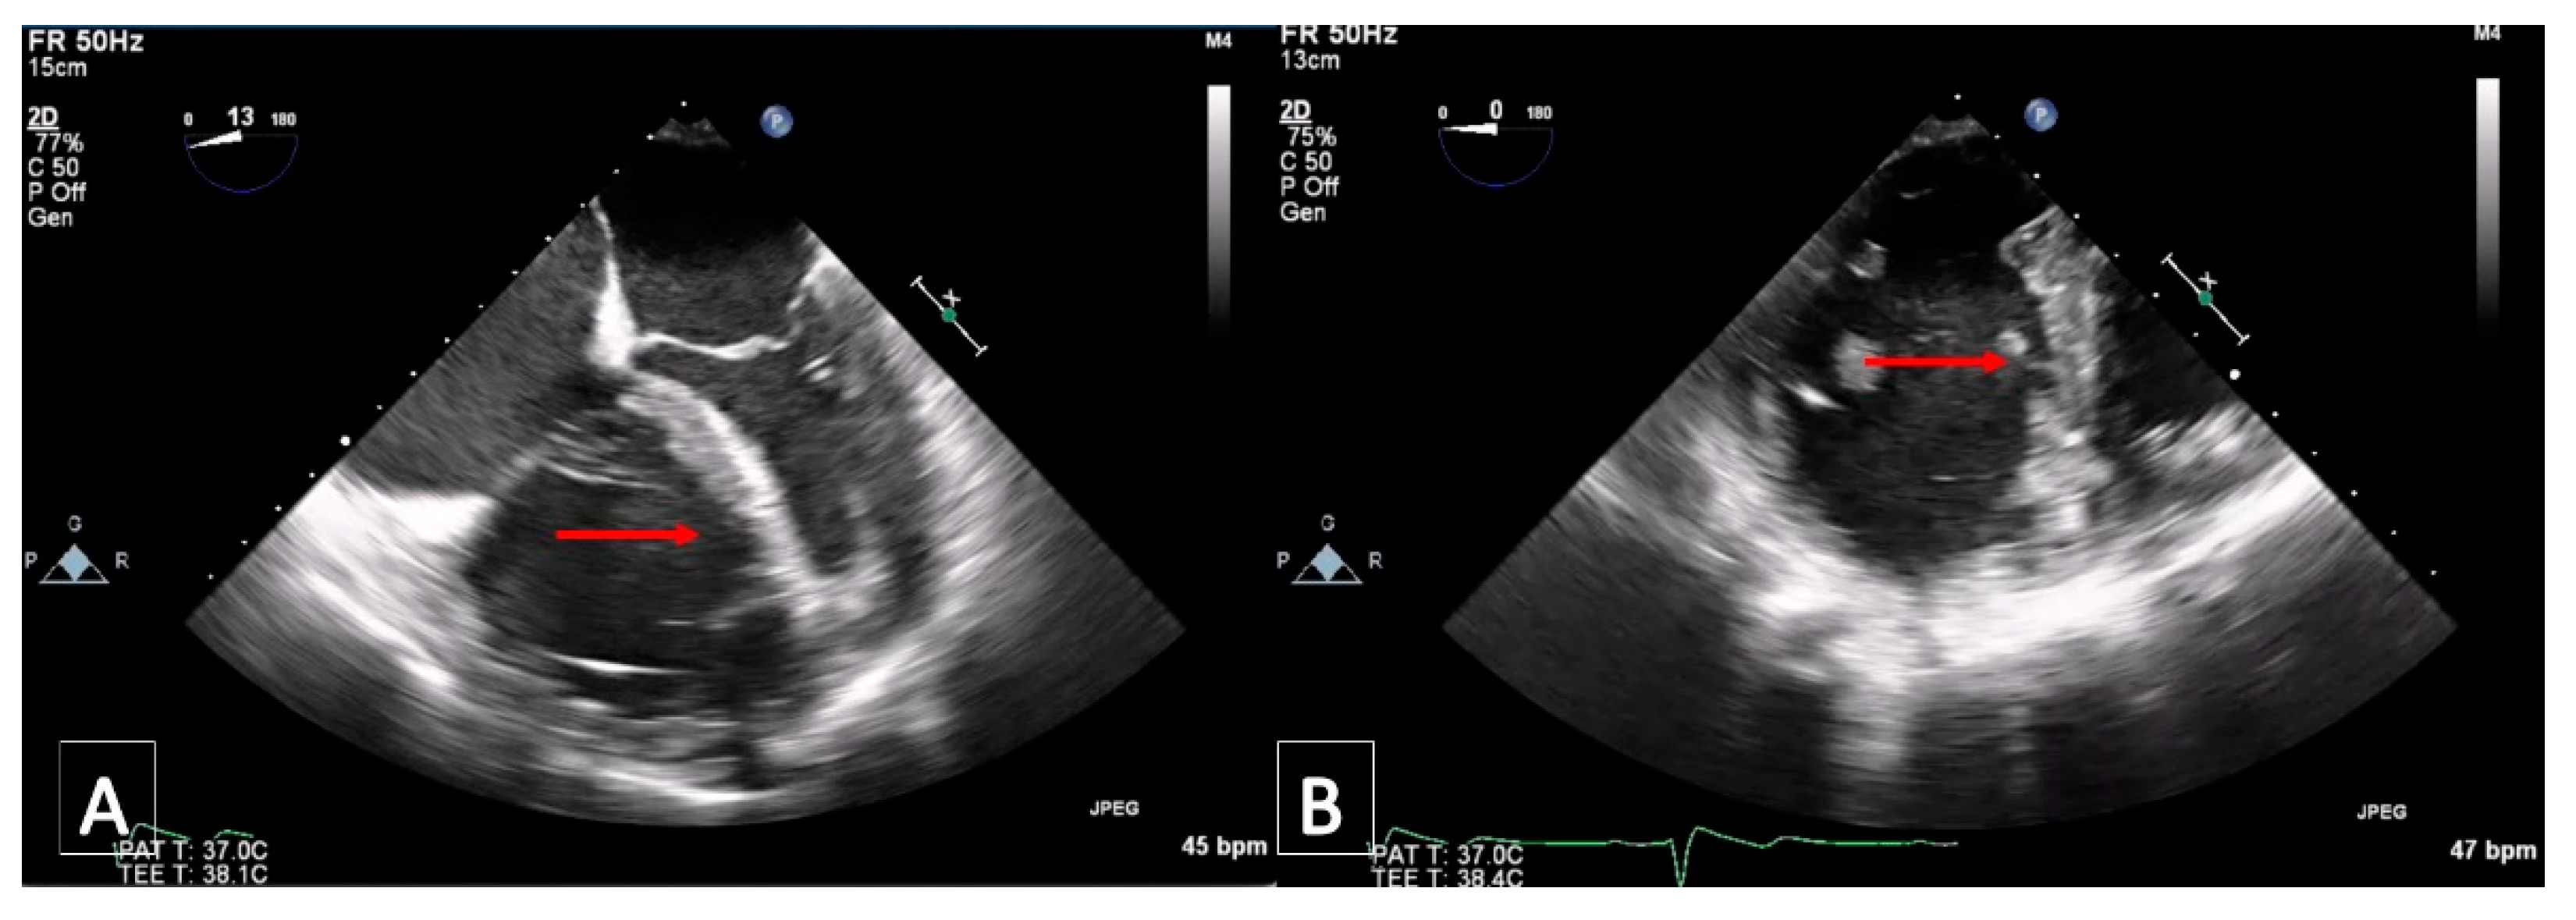

2.2. Case 2

3.5. Transthoracic Echocardiography